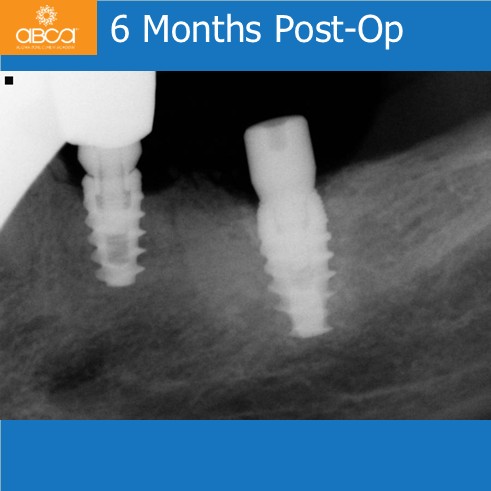

The patient presented with an infected and fractured molar with compromised buccal plate. The extraction was done in segments. Osteotomy prep grafted with Bond Apatite®, uncover osteotomy, immediate implant placement. Note the keratinized gingiva around the healed implant. The key here was no flap at the time of the extraction.